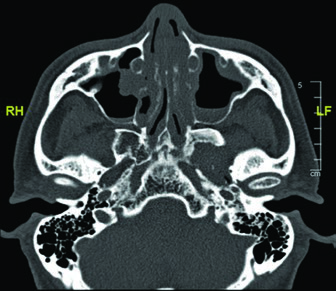

Bone involvement requires specific assessment using bone windows on CT. The image shows periosteal reaction at the posterior aspect of the left mandibular ramus, suggesting direct involvement. When confirmed, the bony structure must be incorporated into the CTV with appropriate margin.

These findings highlight the importance of a thorough imaging study before simulation. The combination of soft tissue and bone windows on the same CT ensures that no tumor extension goes undetected.